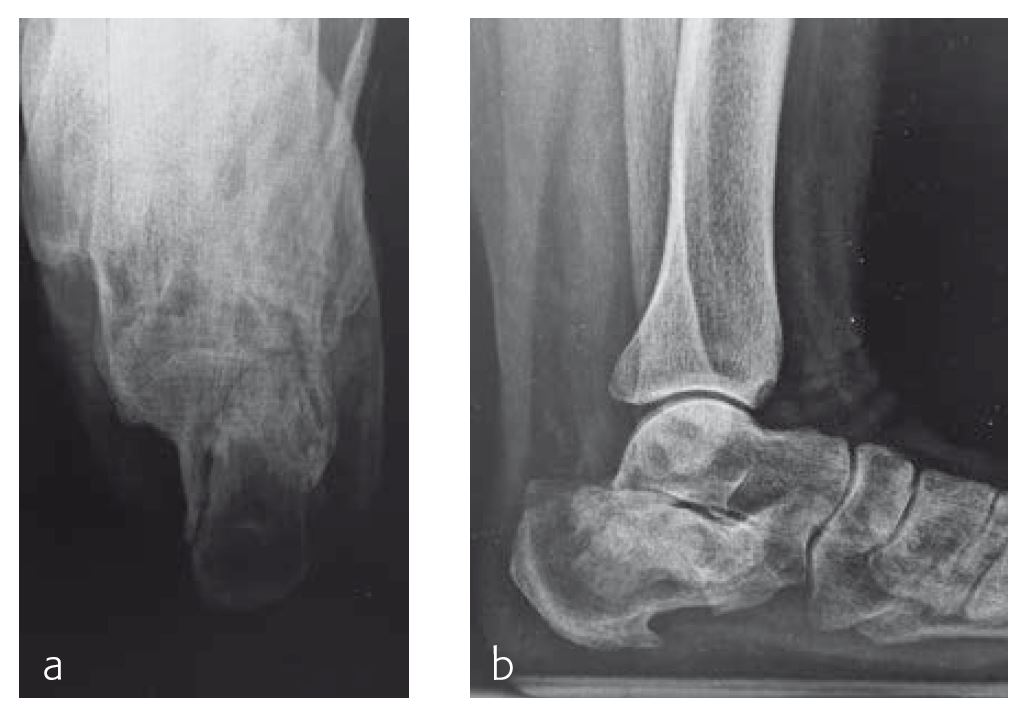

Case 1: Ladder fall

A 58-year-old woman (Fig 1), who had fallen from a ladder 9 weeks earlier, had indications of a malunited fracture and was referred to the clinic by a family physician.